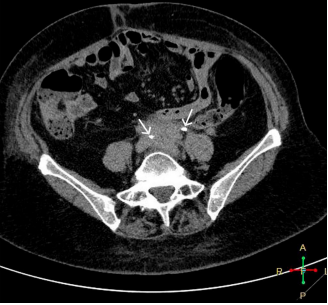

The patient's laboratory values improved notably and a new MDCT of the abdomen and pelvis with intravenous contrast was performed 3 months after hospital discharge, where the retroperitoneal image described above was no longer evident (Figure 3 and 4).1-8

Figure 4 MDCT with intravenous contrast, arterial phase, axial view. Aortic bifurcation is recognized, with slight rarefaction of the retroperitoneal fat.